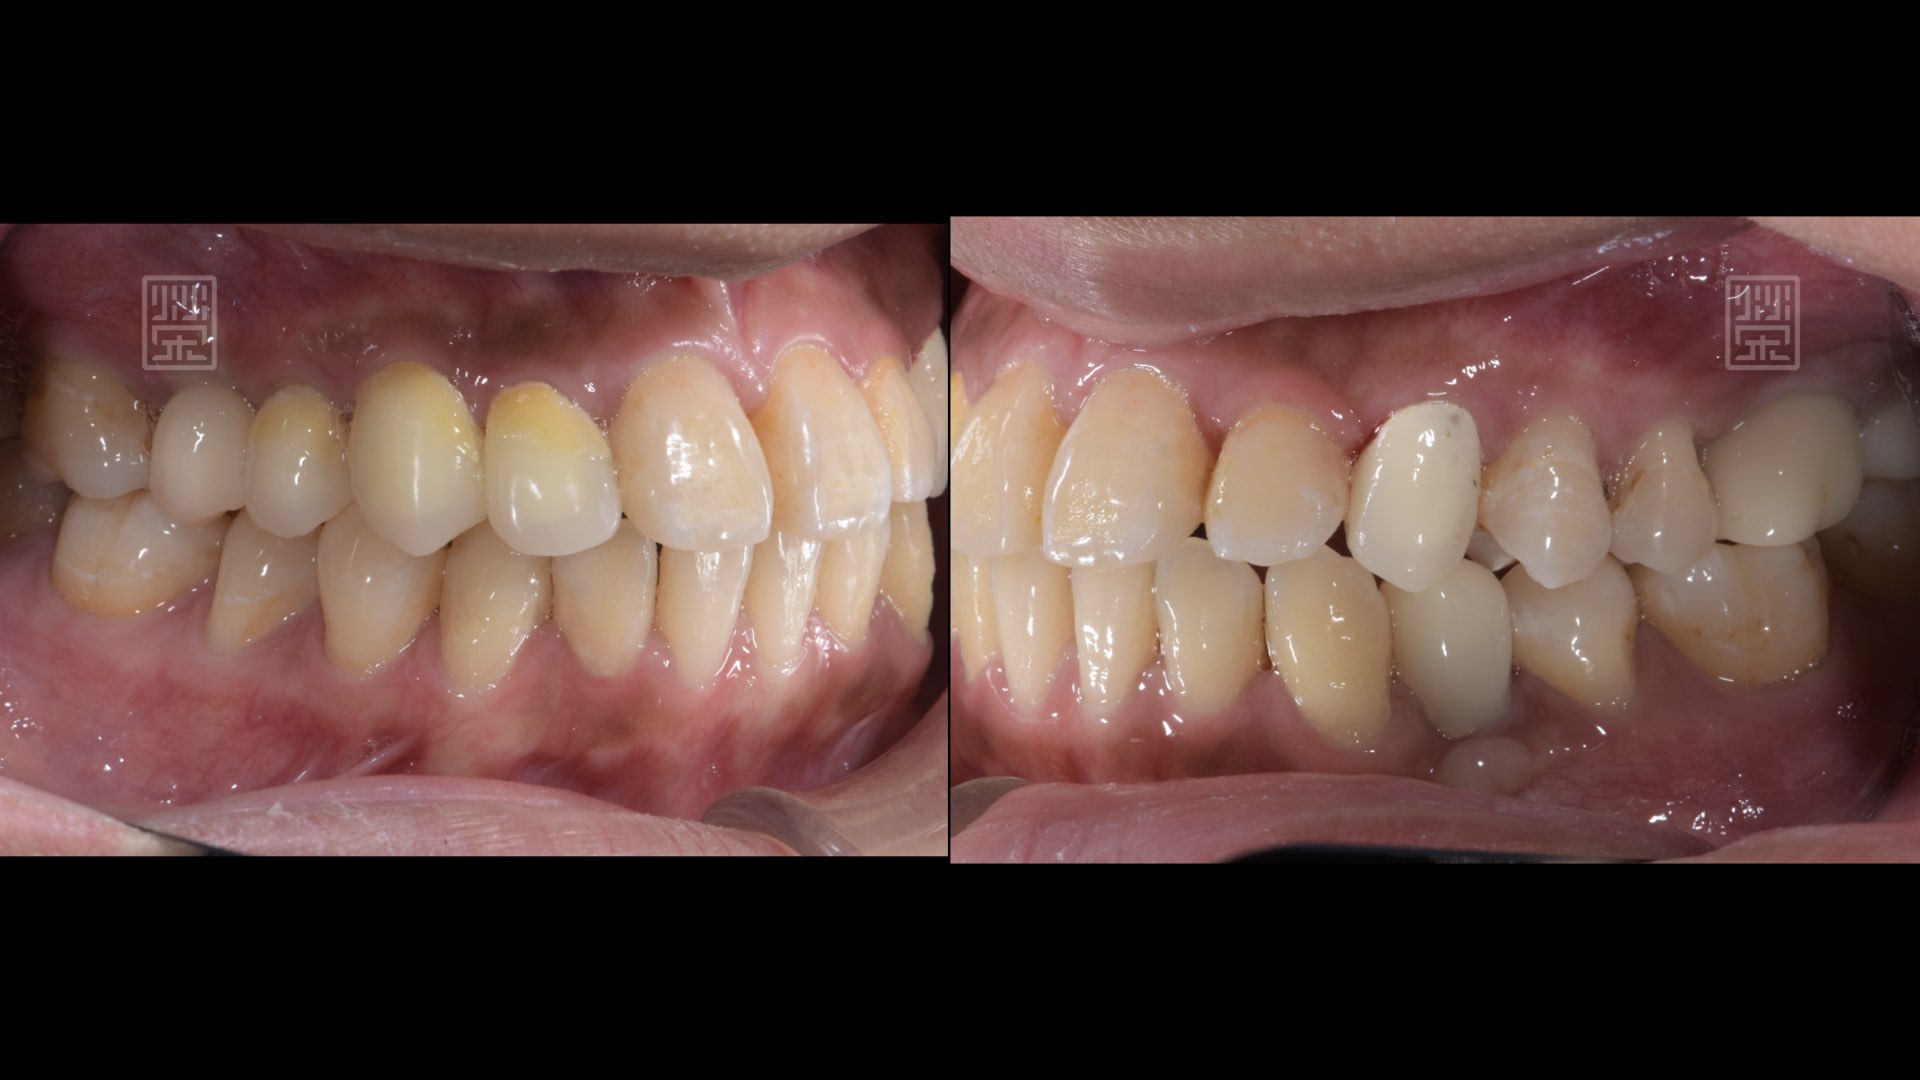

全瓷冠、植牙修復完成